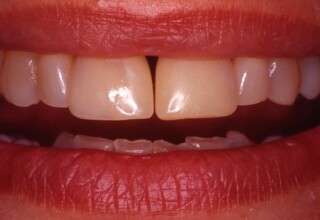

Whitening of non-vital teeth

Teeth with a root canal often lose their brightness and darken to an unesthetic level. Their bleaching requires an excellent root canal and patience. An adhesive filling is placed inside the root to confine the bleaching effect to the tooth part which is visible in the oral cavity. The actual bleaching may require 1-5 short sessions for the placement and renewal of the bleaching material. After the bleaching a high quality adhesive filling is mandatory.

Initial appearance

Final appearance